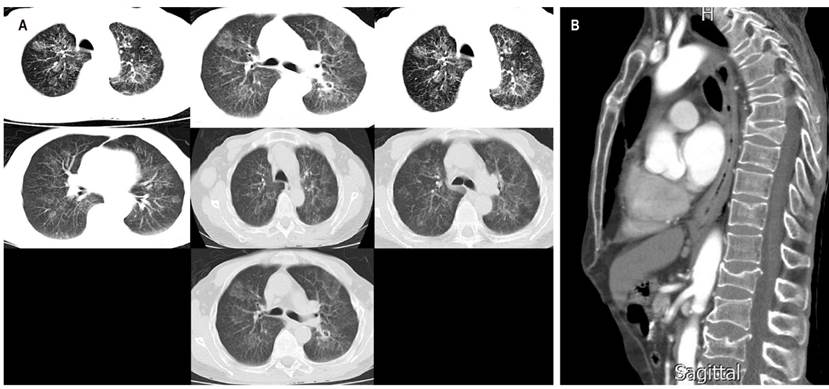

Al ingreso, en revisión por sistemas, refirió tos no productiva ocasional sin disnea y pérdida de peso de 10 kg en el último mes; se encontró al paciente estable, sin respuesta inflamatoria sistémica, signos vitales sin alteraciones, con índice de masa corporal (IMC) de 17 kg/m² y signos de deshidratación grado I. Se sospecha inicialmente de síndrome constitucional secundario a neoplasia de origen gastrointestinal, por lo que fue llevado a EVDA (Figura 1), se tomaron biopsias y se solicitaron estudios de extensión como tomografía de tórax (Figura 2A) con hallazgo de lesiones en el árbol de gemación y obstrucción esofágica a nivel del esófago en el tercio medio y distal (Figura 2B). Se descartó una infección por tuberculosis con 3 baciloscopias seriadas y cultivos negativos, enzimoinmunoanálisis de adsorción (ELISA) para virus de la inmunodeficiencia humana (VIH) negativo y hemograma dentro de los límites normales. El estudio histopatológico (Figura 3) de la biopsia esofágica evidenció una enfermedad granulomatosa crónica no necrotizante secundaria a infección micótica; la coloración de plata metenamina confirmó la presencia de levaduras extracelulares, con gemación de base angosta y formación de estructuras similares al “timón de barco” compatibles con PCM. Fue llevado a dilatación con balón a nivel esofágico y colocación de stent, y se inició un tratamiento con itraconazol en cápsulas de 100 mg cada 24 horas al día por 6 meses con el que presentó mejoría de disfagia y síntomas respiratorios; sin embargo, no se cuenta con un registro de seguimiento imagenológico postratamiento.

Figura 2 A. Tomografía de tórax de alta resolución en el que se evidencia compromiso parenquimatoso intersticial generalizado con hiperdensidades en el árbol en gemación. B. Tomografía de tórax de corte sagital que evidencia obstrucción esofágica a nivel del esófago en el tercio medio y distal.

En el presente caso se tienen en cuenta varios factores de riesgo para contraer el agente infeccioso, tales como el área geográfica donde reside o labora y el sexo del paciente. Su grupo etario lo predispone a debutar con enfermedad crónica reactivada; además de la cronicidad de evolución clínica, presenta síndrome constitucional evidenciado por la pérdida involuntaria de peso; afectación pulmonar, manifestada por tos sin expectoración y disnea ocasional, los cuales pueden explicarse por el compromiso del parénquima pulmonar (Figura 2) y afectación esofágica, definidos por disfagia progresiva, que a su vez se demuestra por los hallazgos imagenológicos en los que se aprecia compromiso endoluminal y estenosis del mismo (Figuras 1 y 2B). El tratamiento consta de los azoles, destacando el itraconazol, el cual tiene mejor tolerancia, absorción y menos efectos adversos, y este fue el que se le administró al paciente con una posterior mejoría del cuadro clínico; también se pueden indicar las sulfonamidas y la anfotericina B, última para casos graves17. Estudios han demostrado que la presencia de comorbilidades y fibrosis pulmonar se asocia con alta morbimortalidad por la exacerbación de la enfermedad de base y complicaciones intrínsecas de la infección, razón por la cual el pronóstico del paciente es bueno ya que hay ausencia de antecedentes patológicos y no hay evidencia de fibrosis pulmonar en los exámenes de extensión solicitados18,19.